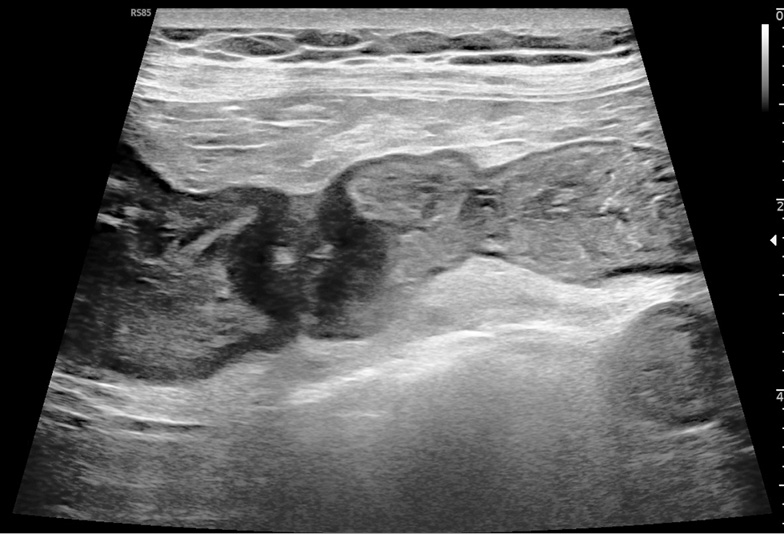

С учетом сохраняющегося явления субкомпенсированного нарушения кишечного пассажа, а также описанных при мультиспиральной компьютерной томографии изменений, было приятно решение выполнить ультразвуковое исследование органов брюшной полости на аппарате экспертного класса с прицельным изучением предположительной зоны поражения. 29.06.2022 выполнено ультразвуковое исследование органов брюшной полости. По его данным, в мезогастрии слева определялся участок тонкой кишки диаметром 15 мм на протяжении 15 мм, стенка толщиной 7–9 мм, гипоэхогенная, аваскулярная, просвет кишки диаметром 2–3 мм, сужен, периодически проходим для содержимого (рис. 1). Приводящий участок тонкой кишки диаметром до 40 мм, стенка не утолщена, перистальтика определяется, содержимое мелкодисперсное эхогенное, перемещение маятникообразное. При динамическом исследовании дистальнее стриктуры тонкая кишка имела участки расширения с маятникообразным перемещением содержимого. Лимфатические узлы в брыжейке увеличены до 19 мм. Результат ультразвукового исследования был трактован как нейроэндокринная (предположительно, гастроинтестинальная стромальная) опухоль тонкой кишки с признаками транзиторного нарушения тонкокишечной проходимости. Увеличение регионарных лимфатических узлов не позволяло исключить злокачественный характер процесса.

Рис. 1. Ультразвуковая картина: образование тонкой кишки, стенозирующее ее просвет